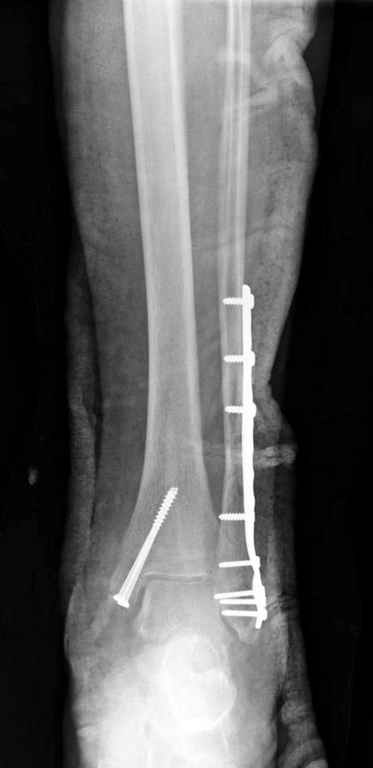

Здесь финальный снимок 73 летней с

сопутствующей шизофренией, латерально бридж

пластину (соединили дистальный конец с диафизом не трогая место перелома) и медиально перкутанно

двумя шурупами. В этам случае без гипса не

обойтись.

Джолдас, Здравствуйте,

Красивые Рг-граммы! У меня нет опыта перкутанной фиксации внутренней лодыжки, поэтому интересно узнать, наблюдали ли вы несращения внутр.лодыжки

Точно, для идеальной репозиции надо открыть передний и задний углы медиальной лодыжки,

сделать ревизию сустава, очистить, убрать интерпозицию, потом только зафиксировать.

Как заметил, по рентгенограмме медиальная лодыжка не очень идеально репонирована. Больная кроме шизофрении страдала другими соматическими заболеваниями, и во время операции от анестезиолога получил рекомендацию поторопиться, поэтому решили закрыто, а так тенденция лечить

открытым методом.

Фиксацию предпочитаю шурупами 4.0 или 3.5мм для медиальной лодыжки, если размер фрагмента позволяет то малым antiglade plate. Шурупом в 4.5 мм не приходилось из-за опасности расколоть лодыжку и из-за большого размера головки. Многие